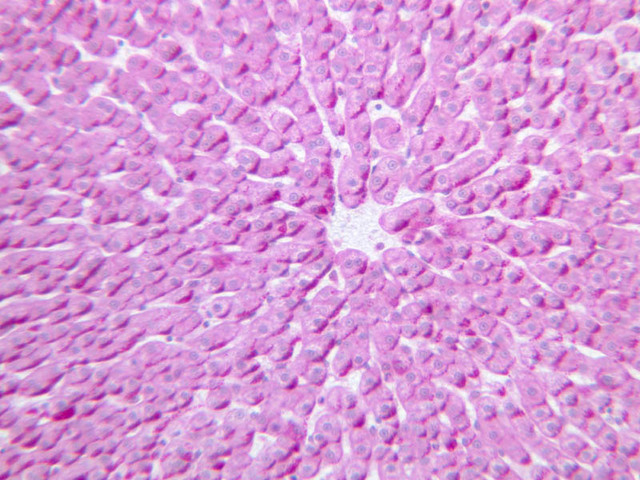

Scan slide B-36 (H&E [10x, 20x] [10x, 20x). Note that in this H&E preparation most of the pancreas consists of rather compactly arranged, darkly stained cells. The compact, darkly stained regions constitute the exocrine portion of the pancreas. (Of what organ does the exocrine pancreas remind you?) The endocrine portions of the pancreas consist of small bits, or islands, of more lightly stained tissue that is somewhat irregularly dispersed within the substance of the exocrine pancreas. Drawing on the name of their discoverer, the endocrine portions of the pancreas are known as the islets of Langerhans.

Using the high dry objective (B-36, H&E [40x, 40x-labeled]), study the structure of several acini. Note that the acinar cells are pyramidal in shape; note also that the acinar cells are clearly polarized: their basal cytoplasm (periphery of acinus) is quite basophilic, owing to large accumulations of RER, whereas their apical cytoplasm contains many acidophilic granules (zymogen granules) (B-36, H&E [10x, 20x, 40x-labeled]).

Now turn your attention to the system of pancreatic ducts. As you look for duct elements, bear in mind that the nuclei of duct cells tend to stain more lightly and to have less prominent nucleoli than do those of acinar cells. Begin by studying a number of different acini until you have identified several examples of centroacinar cells, which represent the initial segment of the duct system. Centroacinar cells are usually evident as lightly stained nuclei that lie, individually or in clusters of two or three, near the center of an acinus. Now look along the boundaries between acini for intercalated ducts (B-36, H&E [10x, 20x, 40x-labeled] [10x, 20x, 40x]), which appear in longitudinal section as trains of elongate, lightly stained nuclei and in transverse section as closely spaced, lightly stained nuclei surrounding a small lumen. Intercalated ducts drain into intralobular ducts, which are distinguished by their larger diameter. It is best to use the 10X objective as you begin your search for intralobular ducts (B-36, H&E [10x, 20x, 40x-labeled] [10x, 20x, 40x]). You want to be on the lookout for arrays of closely spaced nuclei surrounding a lumen. Conclude your study of the duct system by examining the connective tissue between pancreatic lobules for interlobular ducts, which may vary in caliber and epithelial lining (B-36, H&E [10x-labeled, 20x, 40x]).

Endocrine pancreas

Although H & E staining permits ready identification of the islets of Langerhans, it does not permit differentiation of the various cell types that comprise the islets (B-36, H&E [10x, 20x, 40x-labeled]). There are no slides in the class collection that permit identification of all of the cell types of the endocrine pancreas. However, the sections on slides B-37 and B-40 permit specific identification of two cell types. Slide B-37 has been stained by the aldehyde fuchsin technique, which lends a magenta coloration to the granules of the insulin-producing B-cells. All other cells in the islets stain a dirty orange color (B-37 [10x, 20x, 40x] [10x, 20x, 40x]). Most of these orange-colored cells are the glucagon-secreting A-cells; however, you should bear in mind that somatostatin-secreting D-cells, as well as APUD cells that secrete pancreatic polypeptide are also scattered about the islet. The section on slide B-40 has been prepared by a silver impregnation method that renders some of the APUD cells in the islets (which appear as “clear cells” in ordinary preparations) dark brown or black (B-40 [10x, 20x, 40x]).